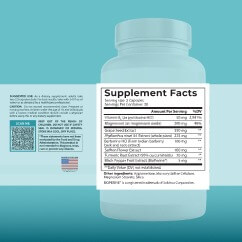

HOW DO YOU USE KIDNEY HEALTH FORMULA?

SUGGESTED USE: As a dietary supplement, take two (2) capsules daily, with a meal and 8 fl oz of water, or as directed by a healthcare professional. Keep out of the reach of children. Do NOT use it if safety seal is damaged or missing. Store in a cool, dry place.